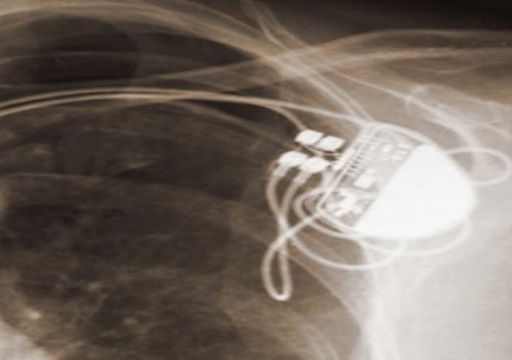

Medical devices like pacemakers and insulin pumps will save many lives, but they also represent an opportunity to computer hackers who would use the Internet to cause havoc.

Criminal Implications of Implantable Medical Devices Since the dawn of the 1970′s television action show the Six Million Dollar Man, the public has been fascinated by bionics and the integration […]